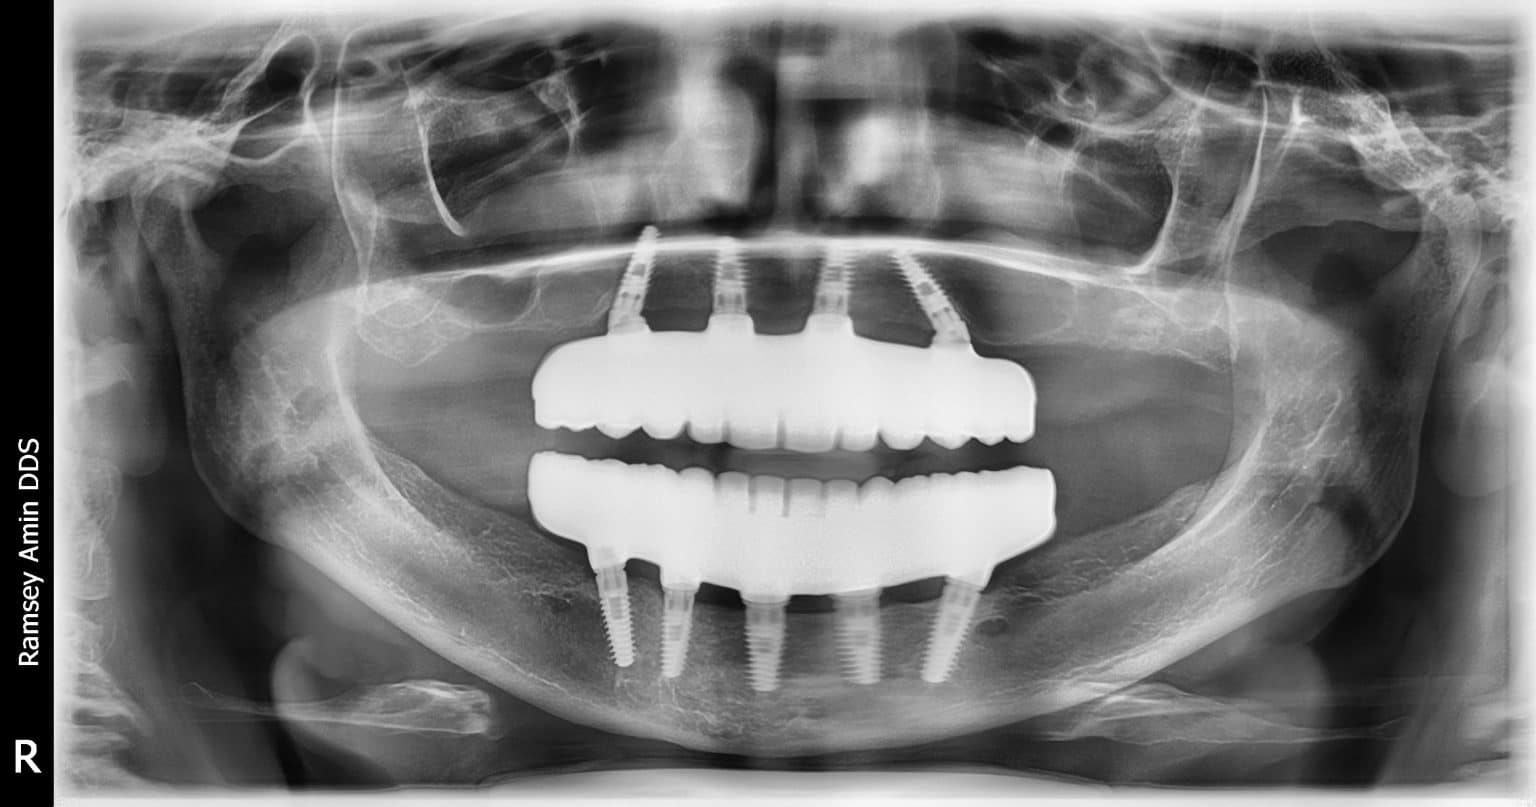

From www.researchgate.net

(A) Panoramic Xray shows 4 dental implants placed in the native and Dental X-Rays And Cochlear Implants the dental patient with a cochlear implant knows that there are surprises with noises that people with normal. As these implants include metal elements, the. a cochlear implant is an electronic device that improves hearing. It can be a choice for people who have severe hearing loss from inner. Likewise, ct scans , which provide good images for. Dental X-Rays And Cochlear Implants.

From drramseyamin.typepad.com

Dental Implant Xrays Dental Implant Dentistry Blog Dental X-Rays And Cochlear Implants Likewise, ct scans , which provide good images for bones, the lungs, blood vessels and the gastrointestinal tract, usually require no special precautions for a. fortunately, she has been successfully treated with bilateral cochlear implants and speech processors. As these implants include metal elements, the. It can be a choice for people who have severe hearing loss from inner.. Dental X-Rays And Cochlear Implants.